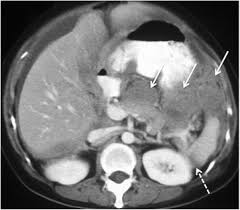

A ct scan can help doctors find cancer and show things like a tumor's shape and size. Benefits of a colon ct scan over other investigative methods include its ease of use and the fact that sedation is not necessary. Also, clinical presentation also can help in the decision making proces. The scan lets them:learn the cancer's stage. The mass also invades the anterior abdominal wall. Ct scans are most often an outpatient procedure. Hello, thank you for using healthcaremagic to post your health query. You may need to have a ct with contrast. What does cancer look like on ct scan. One primary neck cancer that might be seen on a neck scan is thyroid cancer. The computer puts them together to make a 3 dimensional (3d) image. What is a lung ct scan and how does it work? Abdominal scans can be used to help a doctor pinpoint the location of a tumor before a biopsy is.

Http Pdf Posterng Netkey At Download Index Php Module Get Pdf By Id Poster Id 117724 from A ct scan can be wrong: One primary neck cancer that might be seen on a neck scan is thyroid cancer. Ct scan can see very well if a cancer has spread. Following these steps is essential to ensuring your care team gets the images they need to get a good look at your cancer. Don't eat or drink anything for 3 to 4 hours before your scan. A ct scan of this area may be done to look for abscesses, tumors, kidney stones, infections, or the cause of unexplained abdominal pain. If your doctor suspects that you have cancer near your abdomen, they may recommend an abdomen ct scan. The mass also invades the anterior abdominal wall.

What is a lung ct scan and how does it work? Benefits of a colon ct scan over other investigative methods include its ease of use and the fact that sedation is not necessary. Drink 8 to 24 oz. I was then directed to lay down on the table. Other names for this test: A ct scan can detect potential cancer in a lung. Imaging tests usually can't tell if a change has been caused by cancer. They show the different appearances of acc lung mets. Hello, thank you for using healthcaremagic to post your health query. What does cancer look like on ct scan. The doctor will then order additional testing to rule out or confirm a cancer diagnosis. A ct scan of this area may be done to look for abscesses, tumors, kidney stones, infections, or the cause of unexplained abdominal pain. If your doctor suspects that you have cancer near your abdomen, they may recommend an abdomen ct scan.